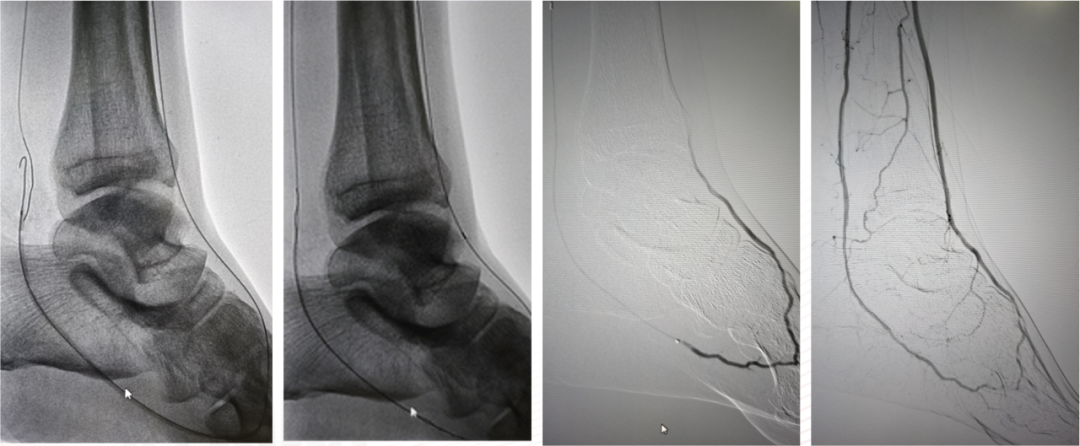

★ 第一足趾感染迁延不愈

Case 7:老年男性患者,第一足趾感染持续不愈达三月余。造影显示胫前动脉远端闭塞,胫后动脉缺如,腓动脉侧支供血不良。术者通过足弓将导丝送入第一足趾动脉,以1.5mm及2.0mm球囊逐级扩张。术后不足一月溃疡愈合,虽三个月后血管再闭塞,但感染未复发,随访两年稳定。

★ 足底外侧动脉的关键作用

Case 9:患者第三、四足趾不愈合,造影显示胫后动脉存在但足底外侧动脉缺如,足底内侧动脉不供应外侧足趾。术者开通胫前动脉后,经足弓将导丝送入足底外侧动脉进行扩张,最终实现足趾愈合。此病例提醒:足底弓的完整性不仅要看主干,还要关注分支动脉的供血范围。